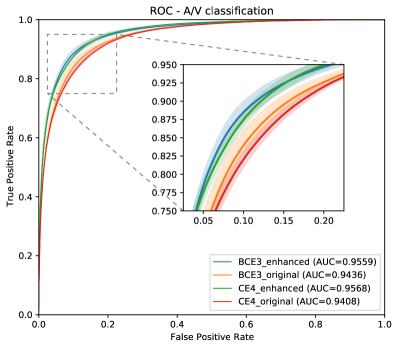

Moreover, the methods in the state of the art report the results for a fixed operating point system, with a varying preference for false positives or false negatives among the works. As this complicates the direct comparison between the state-of-the-art results, we complement the results in Tables 4 and 5 with the ROC curves in Figure 15, for the artery/vein classification and the vascular segmentation tasks. In these graphs, we represent the ROC curves for our proposed system (BCE3 loss and enhanced retinographies as input) along with the point representations of the systems in Tables 4 and 5.

As it can be observed in the comparison results, the proposed approach achieves highly competitive results in both the artery/vein classification and the vascular segmentation tasks. In this regard, it is especially relevant that our approach achieves the best performance in the vascular segmentation task among the works aiming at solving both SSCAV tasks, and even a competitive performance with the state-of-the-art specialized methods. This is particularly relevant since, in a real A/V classification scenario, only the detected vessels would be classified into arteries and veins. Regarding the artery/vein classification of the ground truth vessels, however, the achieved results are slightly below the most recent works [40, 41].

In order to provide insight on the comparison results, it should be noticed that our method proposes a straightforward application of a plain U-Net architecture [49], to full resolution images, by simply adjusting the used loss. Thus, the research herein described aims at providing methodological advances by simplifying the used methods, gaining insight on why they work, taking advantages of more appropriate ways of posing the end-to-end training of the target tasks, and avoiding the use of any bells and whistles. In this regard, some of the prior works trained and applied the networks to a patch-wise [37, 40], instead of using the full-size images as our case. We think that it is more convenient to take full advantage of the FCNN architectures to pose end-to-end training approaches that use full-size images as inputs, even if the patch-wise balancing and the augmentation approaches can take minor advantages on the results, depending on the used datasets. Several methods, including the best performing ones, used ad hoc weights to adjust the importance of each class on the loss [38, 40, 41], or even heuristic weights to balance the importance of each vessel within each image [40, 41]. While we could adjust the class weights, as well as the importance of the difficult target structures, to improve the overall provided results of our approach, we think that such approach requires appropriate validation methodologies that are not usually practical giving the large training times of deep neural networks. There are also interesting ideas which can boost the performance of any approach, and could be potentially applied to our approach in future work, such as the use of pretrained networks [40, 41] (ours are trained from scratch), enforcing the vascular tree classification coherence using an ad hoc postprocessing approach [37, 41], or the use of deep supervision to enhance the backpropagation of gradients [40, 41]. Notwithstanding we did not include any of these mechanisms, the achieved results are highly competitive in artery/vein classification, and certainly better in the vascular segmentation, which emphasizes the potential of the proposed approach.